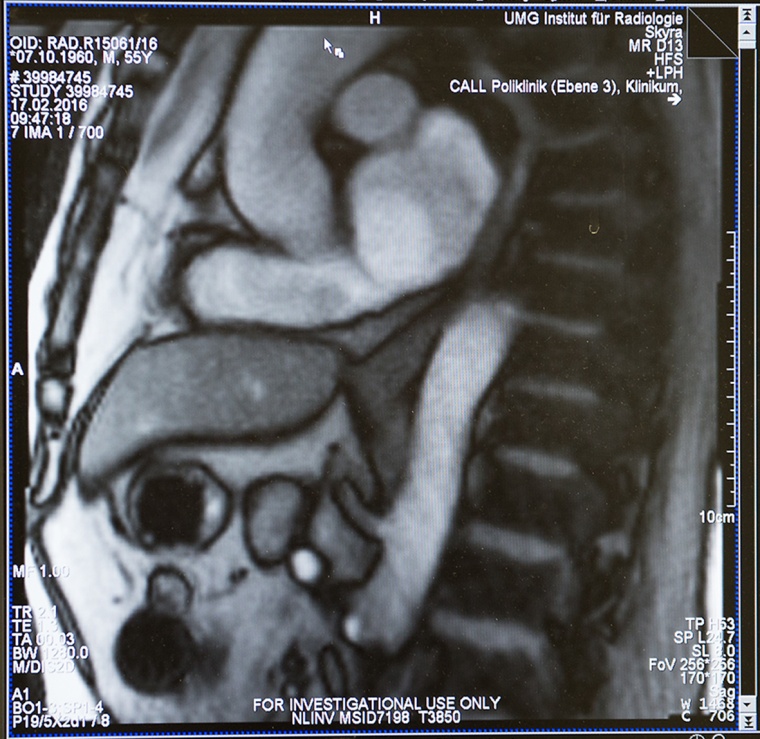

Den Vorgang des Schluckens mit bildgebenden Verfahren darzustellen, das war bisher nicht möglich. Göttinger Ärzten und Forschern ist dies zum ersten Mal weltweit gelungen. Sie haben einen Weg für eine filmische Darstellung des Schluckens gefunden. Die neue Methode zur Darstellung des Schluckvorgangs hat eine interdisziplinäre Arbeitsgruppe von Ärzten der Universitätsmedizin Göttingen (UMG) und Forschern des Max-Planck-Instituts (MPI) für biophysikalische Chemie, Göttingen, erarbeitet. Das Göttinger Forscherteam nutzt dafür das Verfahren der Magnetresonanz-Tomografie (MRT) in Echtzeit. Mit Hilfe dieser Technik, der „Echtzeit-MRT“, kann der Schluckakt mit 25 Bildern pro Sekunde dokumentiert und untersucht werden. Das Echtzeit-MRT liefert Bilder, die für diagnostische Zwecke in der Klinik und für die Behandlung nutzbar sind. Ursachen von Sodbrennen oder Schluckstörungen lassen sich genauer erkennen und untersuchen. Für eine individuelle und gezielte Behandlung der Volkskrankheit Sodbrennen eröffnen sich damit neue Wege.

Die Echtzeit-MRT liefert Bilder, mit denen der Schluckvorgang vom Mundraum durch die Speiseröhre bis zum Mageneingang verfolgt werden kann. Auch der Reflux, der entscheidende Akt für Sodbrennen, lässt sich unmittelbar beobachten: Um den Eintritt von Magensäure in die Speiseröhre auszulösen, reicht eine einfache Pressung auf den Bauch des Patienten. „Auf diese Weise lässt sich Sodbrennen diagnostizieren. Gleichzeitig können wir auch die anatomische oder funktionelle Veränderung entdecken, die dem Sodbrennen zugrunde liegt. Wir können jetzt ganz genau sehen, was die Ursache ist: Das kann eine verzögerte Muskelbeweglichkeit (Peristaltik) der Speiseröhre sein oder eine Störung des Übergangs von der Speiseröhre in den Magen oder eine Entleerungsstörung des Magens in den Darm“, so Priv.-Doz. Dr. Beham.